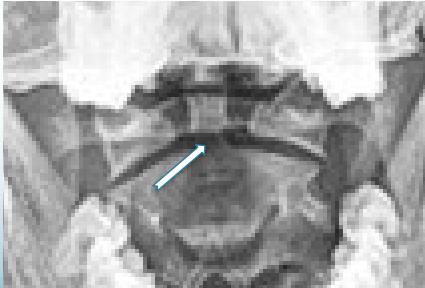

Open-Mouth View

- For C1 and C2

- Odontoid fractures

- Lateral mass fractures

- Look for:

- Symmetry

- Continuity of bone

Fractures of C2-Odontoid

- Identified easily by:

- Open mouth view

- CT scan